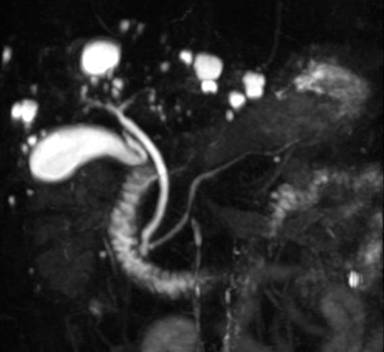

A 53-year-old man was incidentally found to have a cystic tumor in the tail of the pancreas after undergoing an abdominal ultrasound (US), which showed a 41x33 mm cystic mass in the pancreatic tail. He had no abdominal symptoms. The tumor markers, including DUPAN 2, and carbohydrate antigen 19-9, were within the normal ranges. The patient was referred to our hospital for further investigations. A contrast-enhanced CT scan (Figure 1) showed a non-enhanced cyst between the spleen and the pancreas with no solid component. Magnetic resonance cholangiopancreatography (Figure 2) revealed that the main pancreatic duct was regular and had no dilatation, and there was no communication between the cyst and the pancreatic duct. Magnetic resonance imaging (MRI) showed a lesion with a slightly high signal on a T1-weighted image; the lesion, which was well circumscribed, was in the tail of the pancreas (Figure 3). MRI on a T2-weighted image also showed the lesion with a high signal. The cystic tumor was negatively visualized on the PET image. Endoscopic ultrasound (EUS) was performed, which showed a 55x31 mm pancreatic tail lesion with a solid and cystic mixed component (Figure 4a). An endoscopic ultrasound-guided fine-needle aspiration biopsy in a trans-gastric approach of this lesion suggested a diagnosis of a benign squamous cyst (Figure 4b).

Figure 3. Abdominal magnetic resonance imaging findings. a. Slightly high intensity on a T1-weighted image. b. High intensity on a T2-weighted image. |